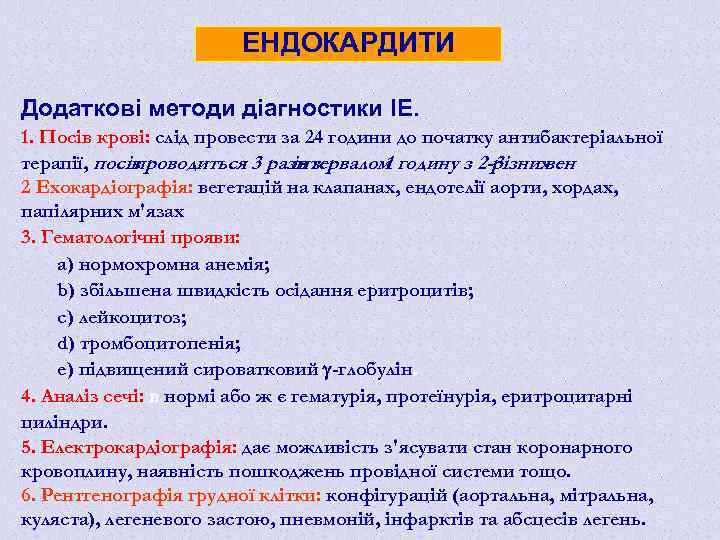

ЕНДОКАРДИТИ Додаткові методи діагностики ІЕ. 1. Посів крові: слід провести за 24 години до початку антибактеріальної терапії, посів проводиться 3 рази з інтервалом годину з 2 -3 1 різних вен 2 Ехокардіографія: вегетацій на клапанах, ендотелії аорти, хордах, папілярних м'язах 3. Гематологічні прояви: а) нормохромна анемія; b) збільшена швидкість осідання еритроцитів; с) лейкоцитоз; d) тромбоцитопенія; е) підвищений сироватковий -глобулін. 4. Аналіз сечі: в нормі або ж є гематурія, протеїнурія, еритроцитарні циліндри. 5. Електрокардіографія: дає можливість з'ясувати стан коронарного кровоплину, наявність пошкоджень провідної системи тощо. 6. Рентгенографія грудної клітки: конфігурацій (аортальна, мітральна, куляста), легеневого застою, пневмоній, інфарктів та абсцесів легень.